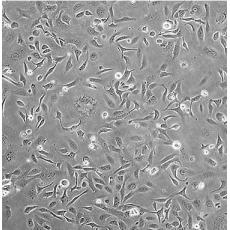

SK-OV-3 [SKOV3]

中文名稱 人卵巢癌細胞

組織來源 卵巢漿液性囊腺癌;腹水轉移;女性

生長特性 adherent

形態(tài)特征 epithelial

細胞描述 SK-OV-3 cells are resistant to tumor necrosis factor and to several cytotoxic drugs including diphtheria toxin, cis-platinum and adriamycin.